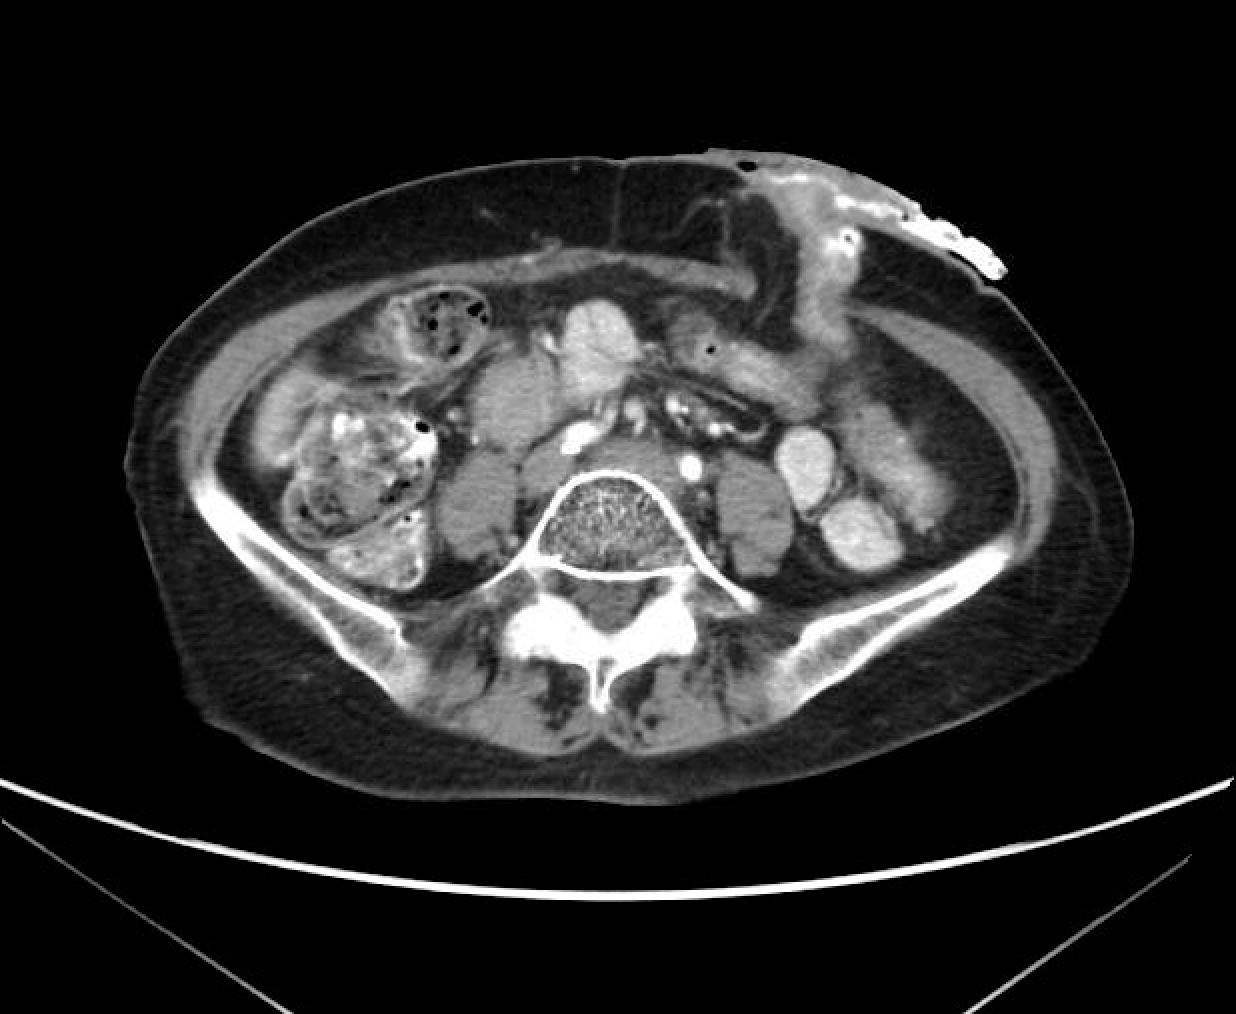

A 65-year-old woman with coronary artery disease and a history of abdominoperineal resection for a low rectal cancer 3 years ago presents with a painless peristomal bulge and an occasional appliance leak. She denies pain and reports normal colostomy output. Examination reveals a pink healthy colostomy and soft bulge medial to the stoma on application of the Valsalva maneuver. Result of recent surveillance computed tomography is available for review (Figure). What is the best management option?